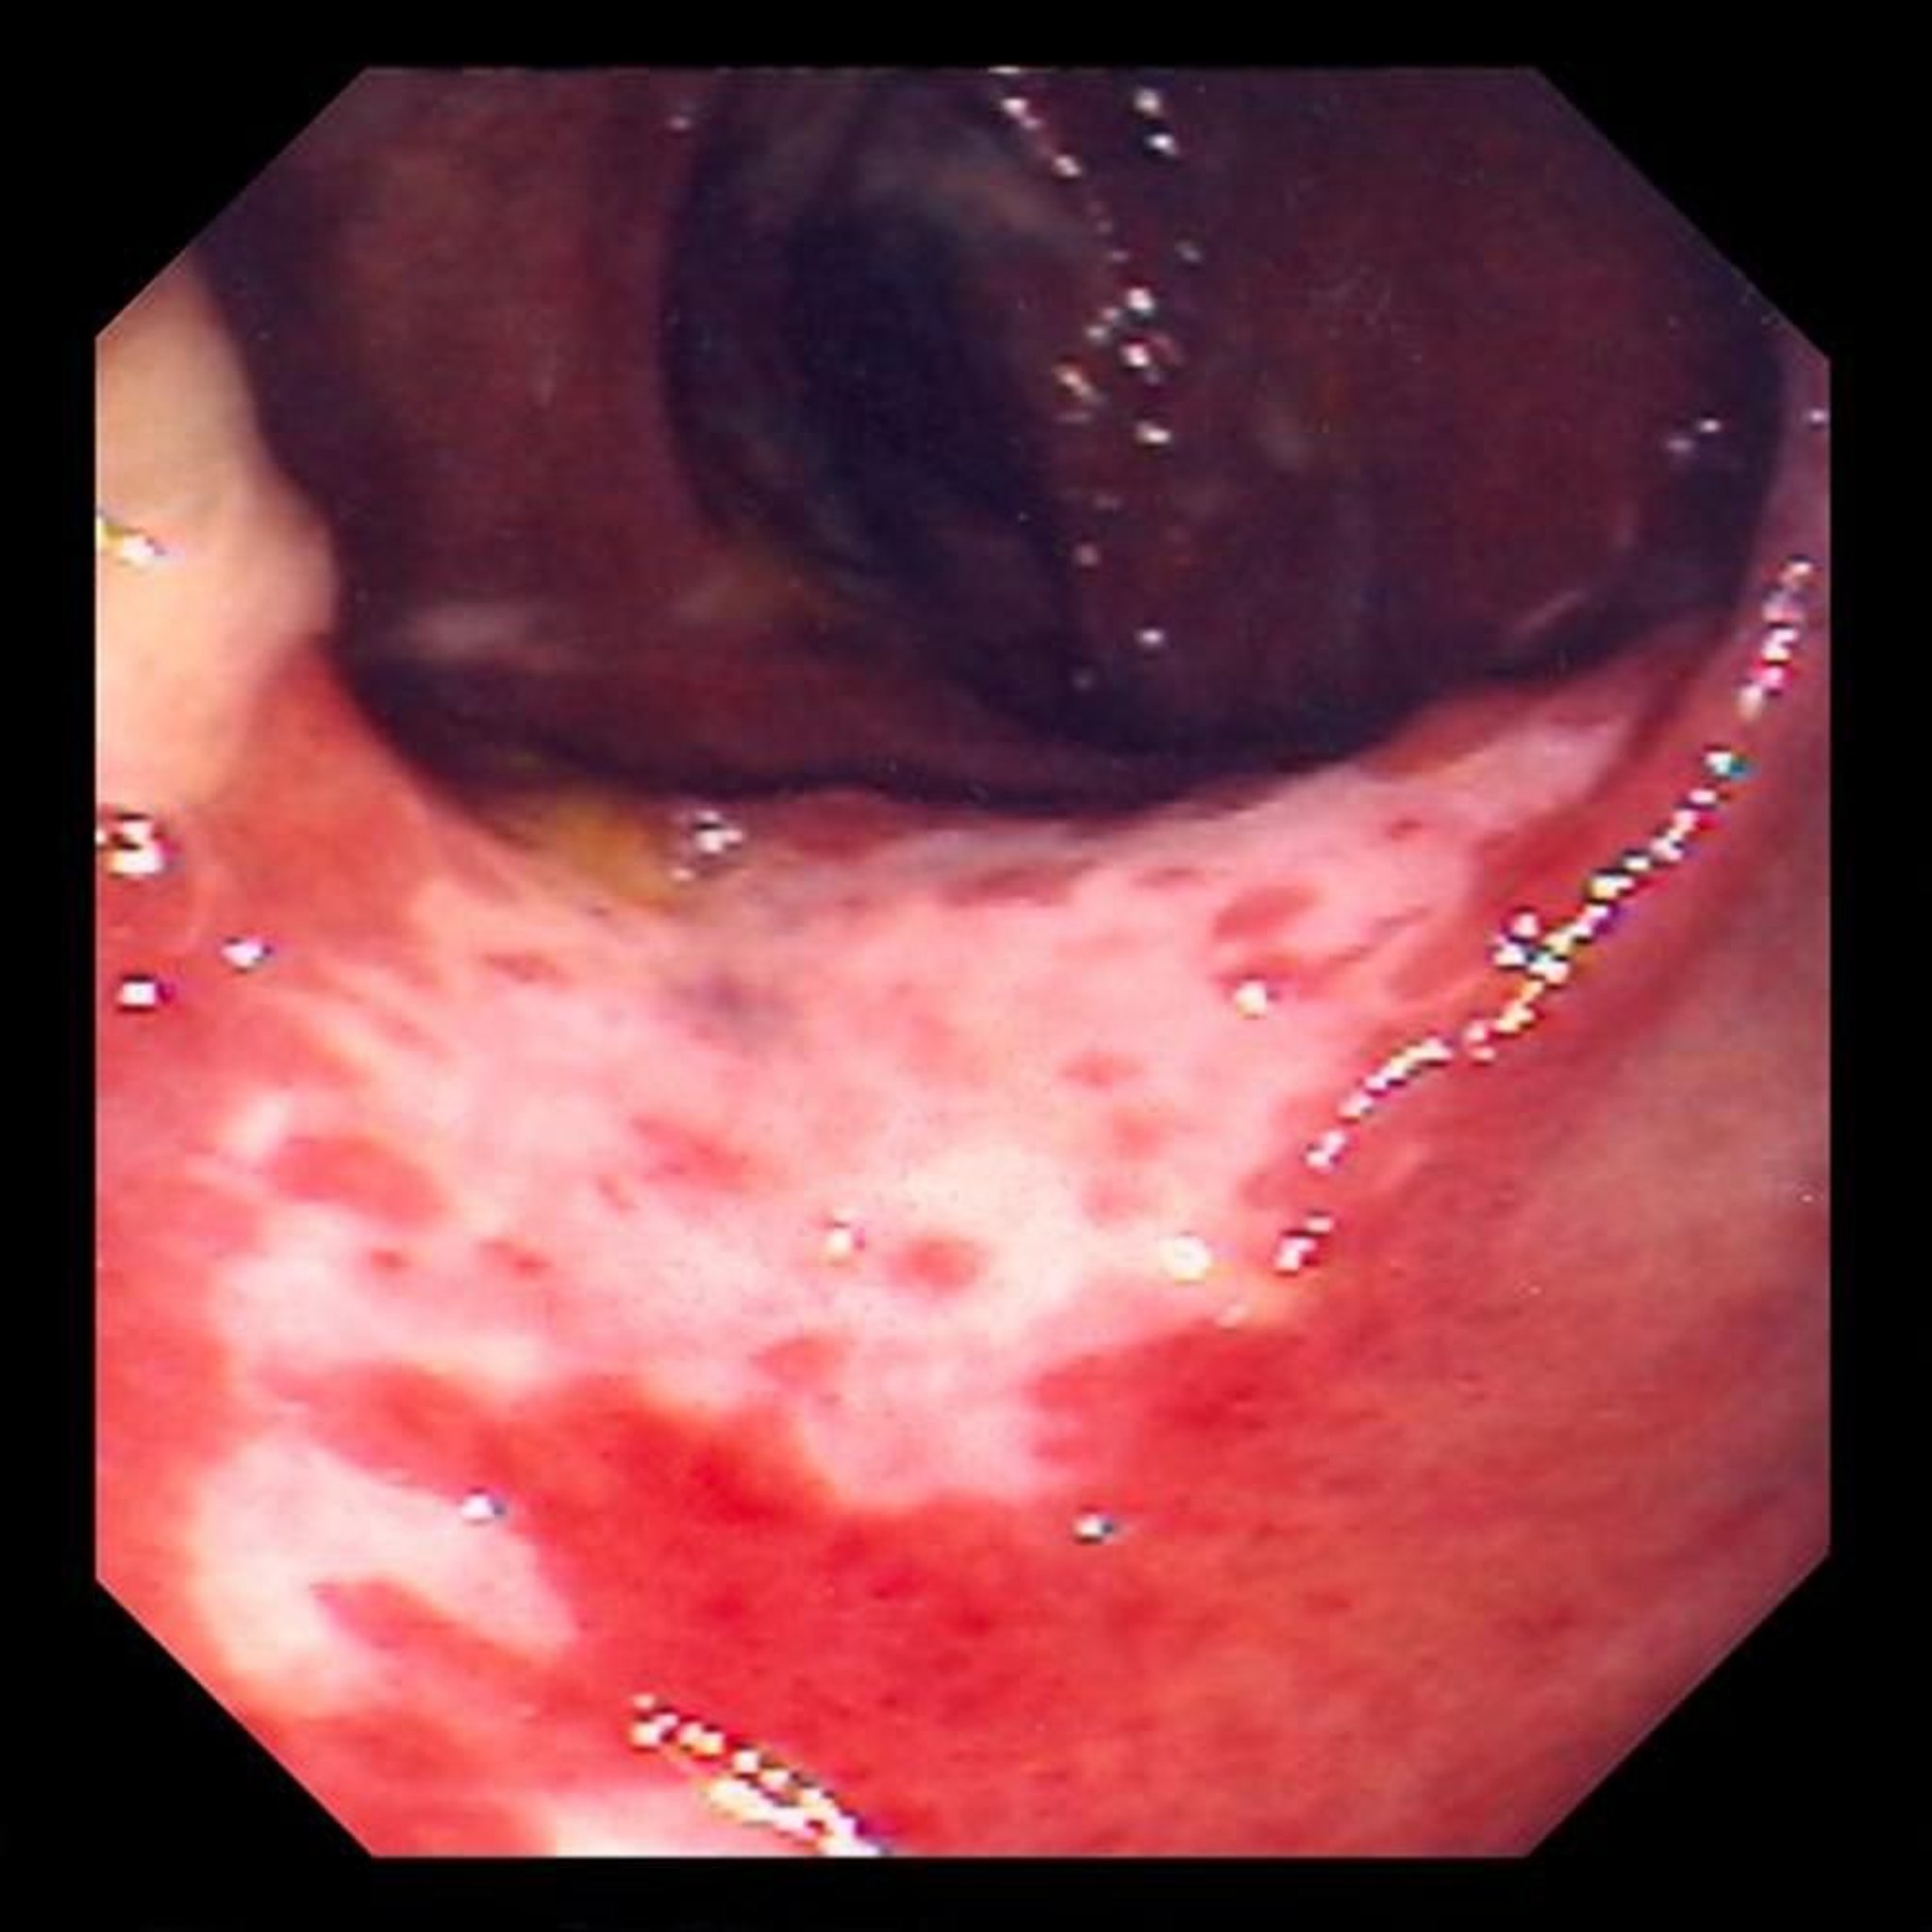

इस्केमिक कोलाइटिस (कोलोनोस्कोपी)

यह तस्वीर रक्त के प्रवाह में रुकावट के कारण आंत की परत को हुए नुकसान को दिखाती है। आंत की परत लाल होती है और अल्सर (सफेद क्षेत्र) से ढकी होती है।

डेविड एम. मार्टिन, MD द्वारा प्रदान की गई तस्वीर।